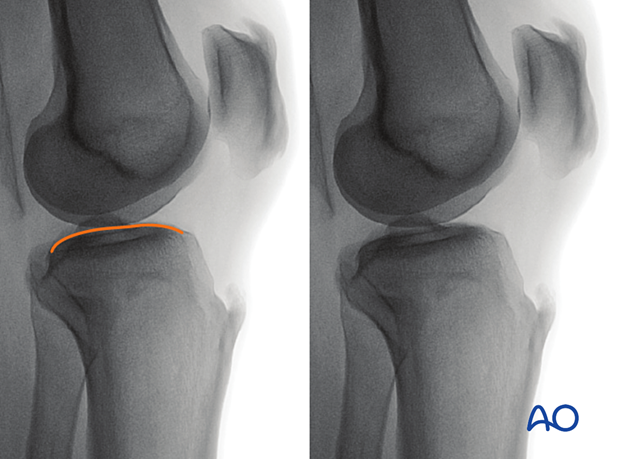

To obtain the optimal lateral view of the distal femur:

The optimal lateral view to the proximal tibia is obtained when:

The following lines and landmarks are seen in the lateral view of the proximal tibia:

The lateral view of the proximal tibia is particularly useful to identify: